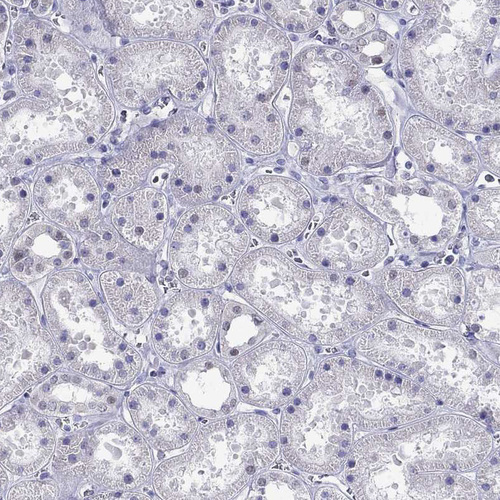

Immunohistochemistry analysis in human testis and pancreas tissues using HPA035531 antibody. Corresponding PPM1G RNA-seq data are presented for the same tissues.